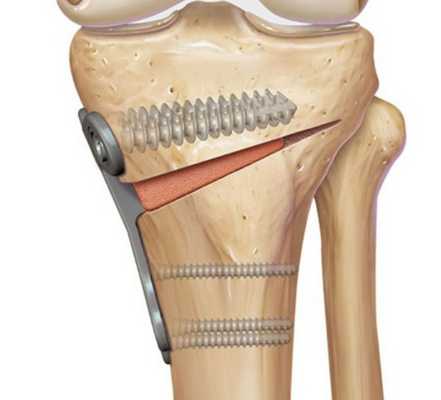

Это оперативное вмешательство, при котором, путем хирургической манипуляции на большеберцовой или бедренной кости, достигается эффект смещения круговой оси распределения нагрузки на нижнюю конечность и придания ей более физиологического положения.

Как проходит операция

Смысл проводимого оперативного вмешательства заключается в том, что на кости со стороны наибольшего поражения сустава делается надрез, отверстие необходимой формы. После этого в это отверстие помещается необходимое количество собственного костного или хрящевого вещества, благодаря чему конечность как бы отводится в сторону, отклоняется по оси тела в противоположном от патологического процесса направлении.

Остеотомия с металлоконструкцией

Далее, участок кости, на котором произведен надрез с помещенным туда костным аутоимплантом, фиксируется титановой пластиной при помощи винтов. Затем доступ ушивается, а конечность иммобилизируется при помощи шины или лангеты. В наложении гипса необходимости нет.

Виды хирургических техник

- по виду доступа - открытая и закрытая. Существуют ситуации, когда открытый доступ, несмотря на большую инвазивность (когда оголяется поверхность кости, а ширина разреза составляет 10 - 12 сантиметров), - предпочтительнее. Необходимость в таком виде вмешательства обусловлена повышенным риском повреждения нервов и сосудов в ходе операции;

- по уровню выполнения вмешательств. В зависимости от локализации патологического процесса и поставленной цели, иссечение производится на бедренной кости или на большеберцовой. На последней, в свою очередь, осуществляются высокая и низкая тибиальные остеотомии;

- по способу иссечения костной ткани - клиновидная, поперечная, прямая, косая, шарообразная;

- по характеру коррекции - открывающая, закрывающая.